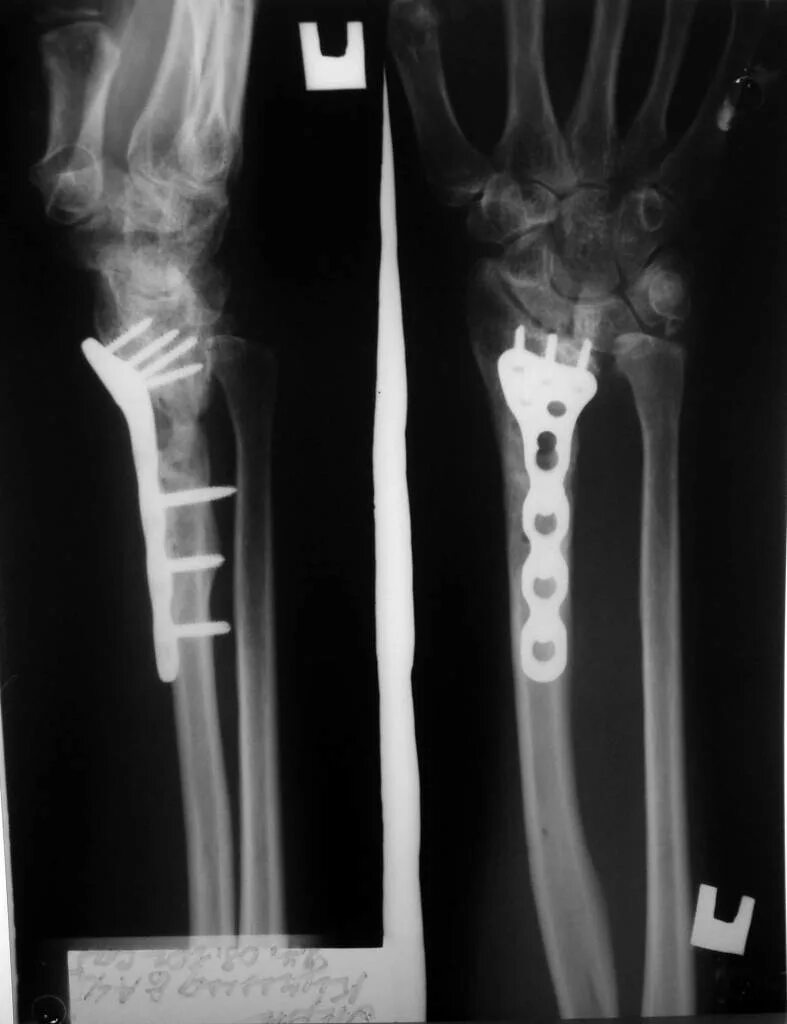

Перелом в типичном месте без смещения